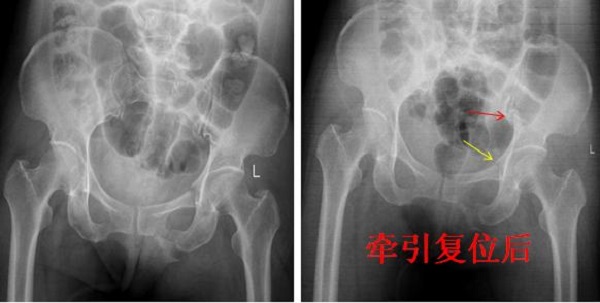

骨盆骨折是创伤骨科最为严重骨折类型之一,传统骨盆骨折手术行切开复位内固定术,手术时间长,创伤大,围手术期出血多,术后患者恢复慢并发症较多。近年来,骨盆骨折微创化治疗成为一种趋势,通过闭合复位或有限切开...